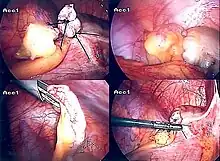

Laparoscopic appendectomy

Laparoscopic appendectomy was introduced in 1983 and has become an increasingly prevalent intervention for acute appendicitis.[90] This surgical procedure consists of making three to four incisions in the abdomen, each 0.25 to 0.5 inches (6.4 to 12.7 mm) long. This type of appendectomy is made by inserting a special surgical tool called a laparoscope into one of the incisions. The laparoscope is connected to a monitor outside the person's body, and it is designed to help the surgeon to inspect the infected area in the abdomen. The other two incisions are made for the specific removal of the appendix by using surgical instruments. Laparoscopic surgery requires general anesthesia, and it can last up to two hours. Laparoscopic appendectomy has several advantages over open appendectomy, including a shorter post-operative recovery, less post-operative pain, and lower superficial surgical site infection rate. However, the occurrence of an intra-abdominal abscess is almost three times more prevalent in laparoscopic appendectomy than open appendectomy.[91]